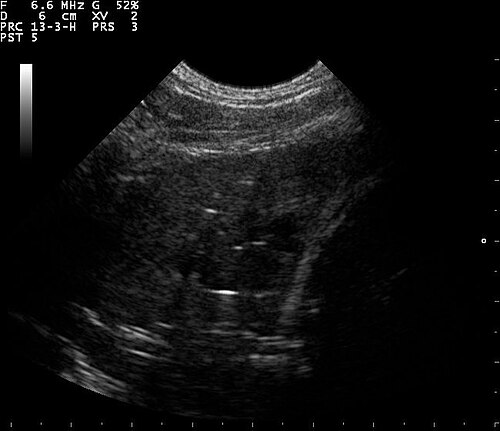

Lung Ultrasound — B-Lines (Pulmonary Fibrosis)

B-lines visible on lung ultrasound indicating interstitial disease in a patient with pulmonary fibrosis

ULTRASOUND Downloaded 2026-03-15

Ultrasound

B Mode

Wikimedia Commons: B lines on a lung ultrasound of a patient with fibrosis.jpg

Lung Ultrasound — Wet Lung (Pulmonary Edema)

Ultrasound image showing wet lung appearance consistent with pulmonary edema

Wikimedia Commons: Ultrasound wet lung 110303143856 1451430.jpg